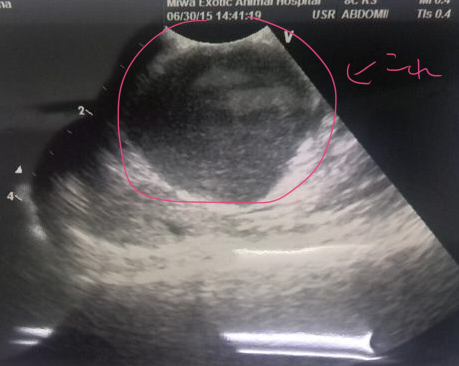

先日病院に行った夜から、お薬はじめたんだけど 食欲もがたっとへって、フードをほぼたべてくれなくなってしまった はなちゃんです。 6月に入って、それまでふやかしフード15~25gくらい食べてくれてたのが 4日から8~13gくらいに減り、でもコオロギやゼリーなどのはなちゃん的に好きなものは 食べていてくれたんですけど、 22日に口の奥の腫れが気になって病院に行った後は フードは0~3g、ゼリーはそれなり食べてくれる、コオロギは元々去年の歯肉炎の時から 頭部のかたいところは切除してやわらかいおなかのところだけあげてたんですが それも外皮部分?をくちゃくちゃやったあとぺっと出すように。 何か食べて貰わないとと思って最近あげてなかったゆで卵の黄身をあげたら ちょっと食べてくれました。 ササミをゆでてミキサーでスープ状にしたのは、最初こそなめてくれたけど 最初以外は興味なくしてしまったみたい… 余りに食べないせいなのか、他に要因があるのか 23日からは左後ろ足が思うようにうごかなくなってきているぽくて ふらつきながら歩く、もしくは左側にぺたっと尻もちをつくというかんじ。 ダックスープを昨日材料届いたので作って出したけど、やっぱりいちど舐めてからは 興味を失ったっぽい。 なので、今朝シリンジでダックスープを少しうすめたものを強制的に口に入れてみたんだけど 最初の一回はとりあえずなめるけど、2回目はもう顔をそむける身体全体で嫌がる、で 食べるということをしたくないのかな~と…身体に食料を入れたくない? 一応25日にみわさんに電話してお薬のせいもあるのかと相談してみたけど それは考えづらいといわれつつ、様子見るために、26.26日とお薬やめてみたけど 薬のせいじゃないっぽい…。 足のふらつきが、最後の方のかのたんを思い出させて うーむ…と思うのですが 食べる事にわりと貪欲なはなちゃんがそれを嫌がるくらいだし ここ一年くらいずっと治療で手術も乗り越えて半年以上たつし、 もうあとは無理にどうこう治療するよりはなちゃんの好きなようにして貰った方が いいのかなあ…なんて考えたりもしています。 食欲が戻ればまた元気になってくれるのかなあ…。 とりあえず食べて貰えるようにいろいろまた試行錯誤します。 そんな近況です。 |